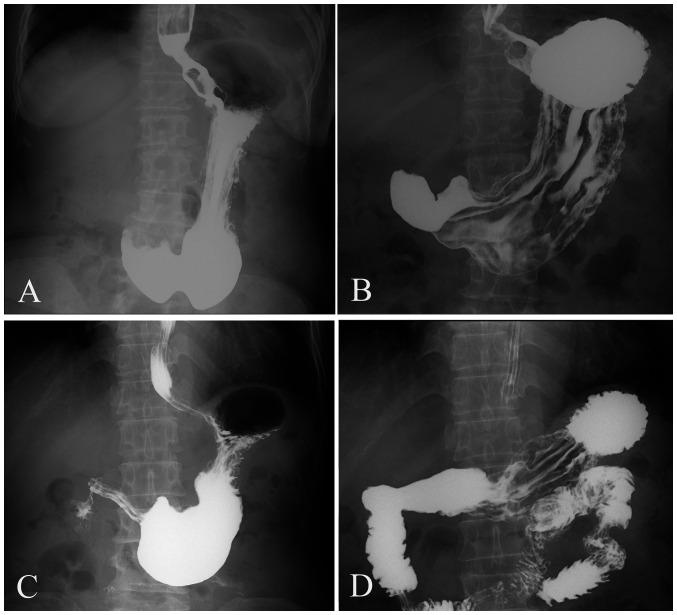

Clinical and pathological features are important factors that affect the prognosis and treatment strategies of patients with gastric cancer (GC). An upper gastrointestinal barium X-ray examination is commonly used to show gastric mucosa and morphological changes. The aim of the present study was to evaluate the association between gastric morphological type and the clinicopathological features of patients with GC, based on double-contrast barium X-ray imaging. A total of 329 patients with GC who underwent upper gastrointestinal barium X-ray examination were analyzed. The gastric morphological type was divided into four types on barium X-ray images: Horn-type, hook-type, weak-type and waterfall-type stomach. The χ test or Fisher's exact test was used to assess the association between gastric morphological type and the clinicopathological features. There was a statistically significant difference in the location of GC between different types of gastric morphology. Hook-type and horn-type GC were commonly present in the lower region of the stomach, while waterfall-type GC was mainly located in the upper region of the stomach. The incidence of waterfall-type non-poorly differentiated GC was higher than that of other gastric types. The incidence of waterfall-type intestinal-type GC was higher than that of other gastric types, and horn-type GC was more common in mixed-type GC. There was a statistically significant difference in the T-staging of GC between different types of gastric morphology. In conclusion, gastric morphological type correlates with the location and T-stage distribution of GC.

临床和病理特征是影响胃癌(GC)患者预后和治疗策略的重要因素。上消化道钡餐X线检查常用于显示胃黏膜及形态变化。本研究的目的是基于双重对比钡餐X线成像评估胃癌患者胃形态类型与临床病理特征之间的关联。对329例行上消化道钡餐X线检查的胃癌患者进行了分析。在钡餐X线图像上,胃形态类型分为四种:牛角型、钩型、无力型和瀑布型胃。采用χ检验或Fisher精确检验评估胃形态类型与临床病理特征之间的关联。不同类型胃形态的胃癌在部位上存在统计学显著差异。钩型和牛角型胃癌常见于胃下部区域,而瀑布型胃癌主要位于胃上部区域。瀑布型非低分化胃癌的发生率高于其他胃型。瀑布型肠型胃癌的发生率高于其他胃型,且牛角型胃癌在混合型胃癌中更为常见。不同类型胃形态的胃癌在T分期上存在统计学显著差异。总之,胃形态类型与胃癌的部位及T分期分布相关。